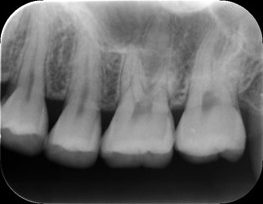

続いて、3~4本ほどのもっと詳細な歯の状態を確認できるのがデンタルレントゲンです。

(デンタルレントゲンでわかること)

・より精密なむし歯の進行状態

・歯と歯の間の見えにくい隣接面のむし歯

・根っこの治療後に薬がしっかり根の先の方まで入っているかどうかの確認

・より精密な歯周病の進行状態(骨の減り具合等)

・根っこの先端に膿がたまっている場合の状態確認

・インプラントの状態や周囲の骨の状態確認

こちらは歯に違和感を感じられたり痛いしみるなどの症状がある場合、撮らせていただいています。